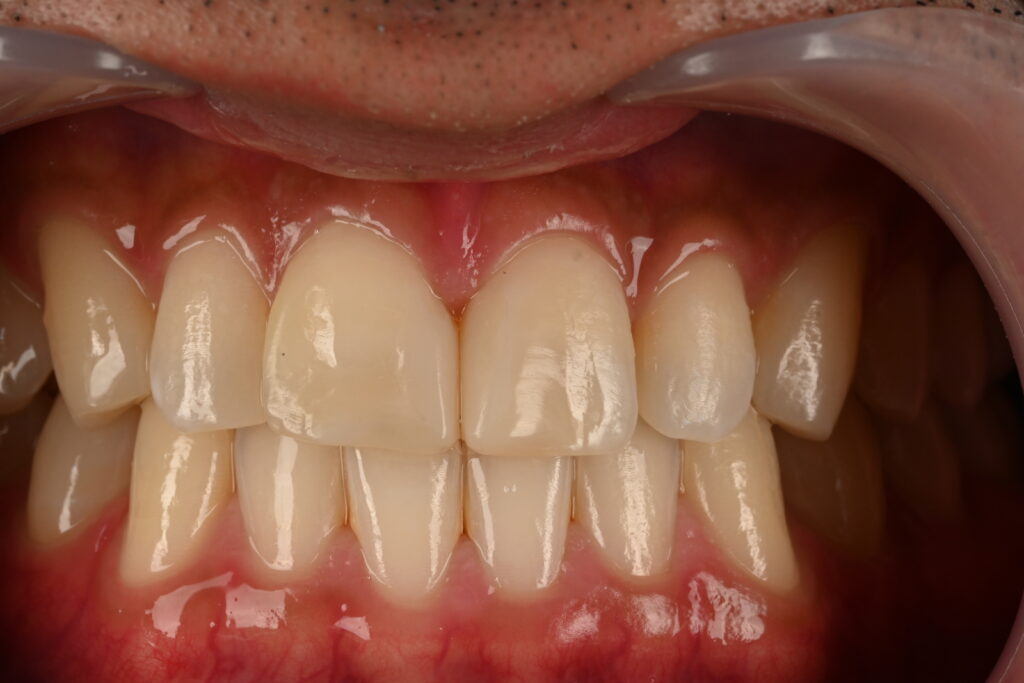

상악동 거상술+점액종 제거술을 본원에서 시행한 후 완료된 사진입니다

가운데 임플란트에 비하여 훨씬 길고 안정되게 식립한 것을 볼 수 있습니다

이정도의 상악동 거상술이면 안정되고 오랜 수명을 생각할 수 있을 듯 합니다